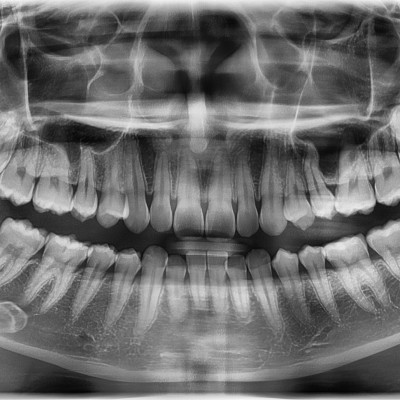

#18,28,38,48 사랑니 발치 #18,28,38,48 사랑니 발치 구강 외과 전문의가 당일 발치했습니다. --------------------..

작성자 이턱이 작성일 01-29 조회 8